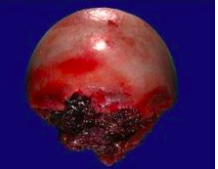

Bosselated

-Having bumps that stick out -Rounded Probuterances